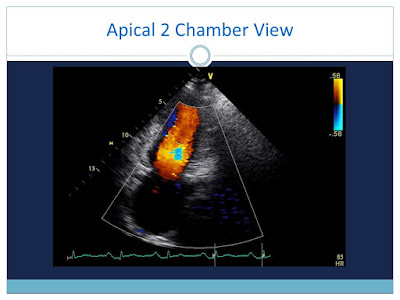

CVT Mohd Farid Case Collection: Case Presentation Of Hypertrophic Cardiomyopathy & Restrictive Cardiomyopathy

Hypertrophic Cardiomyopathy

Restrictive Cardiomyopathy